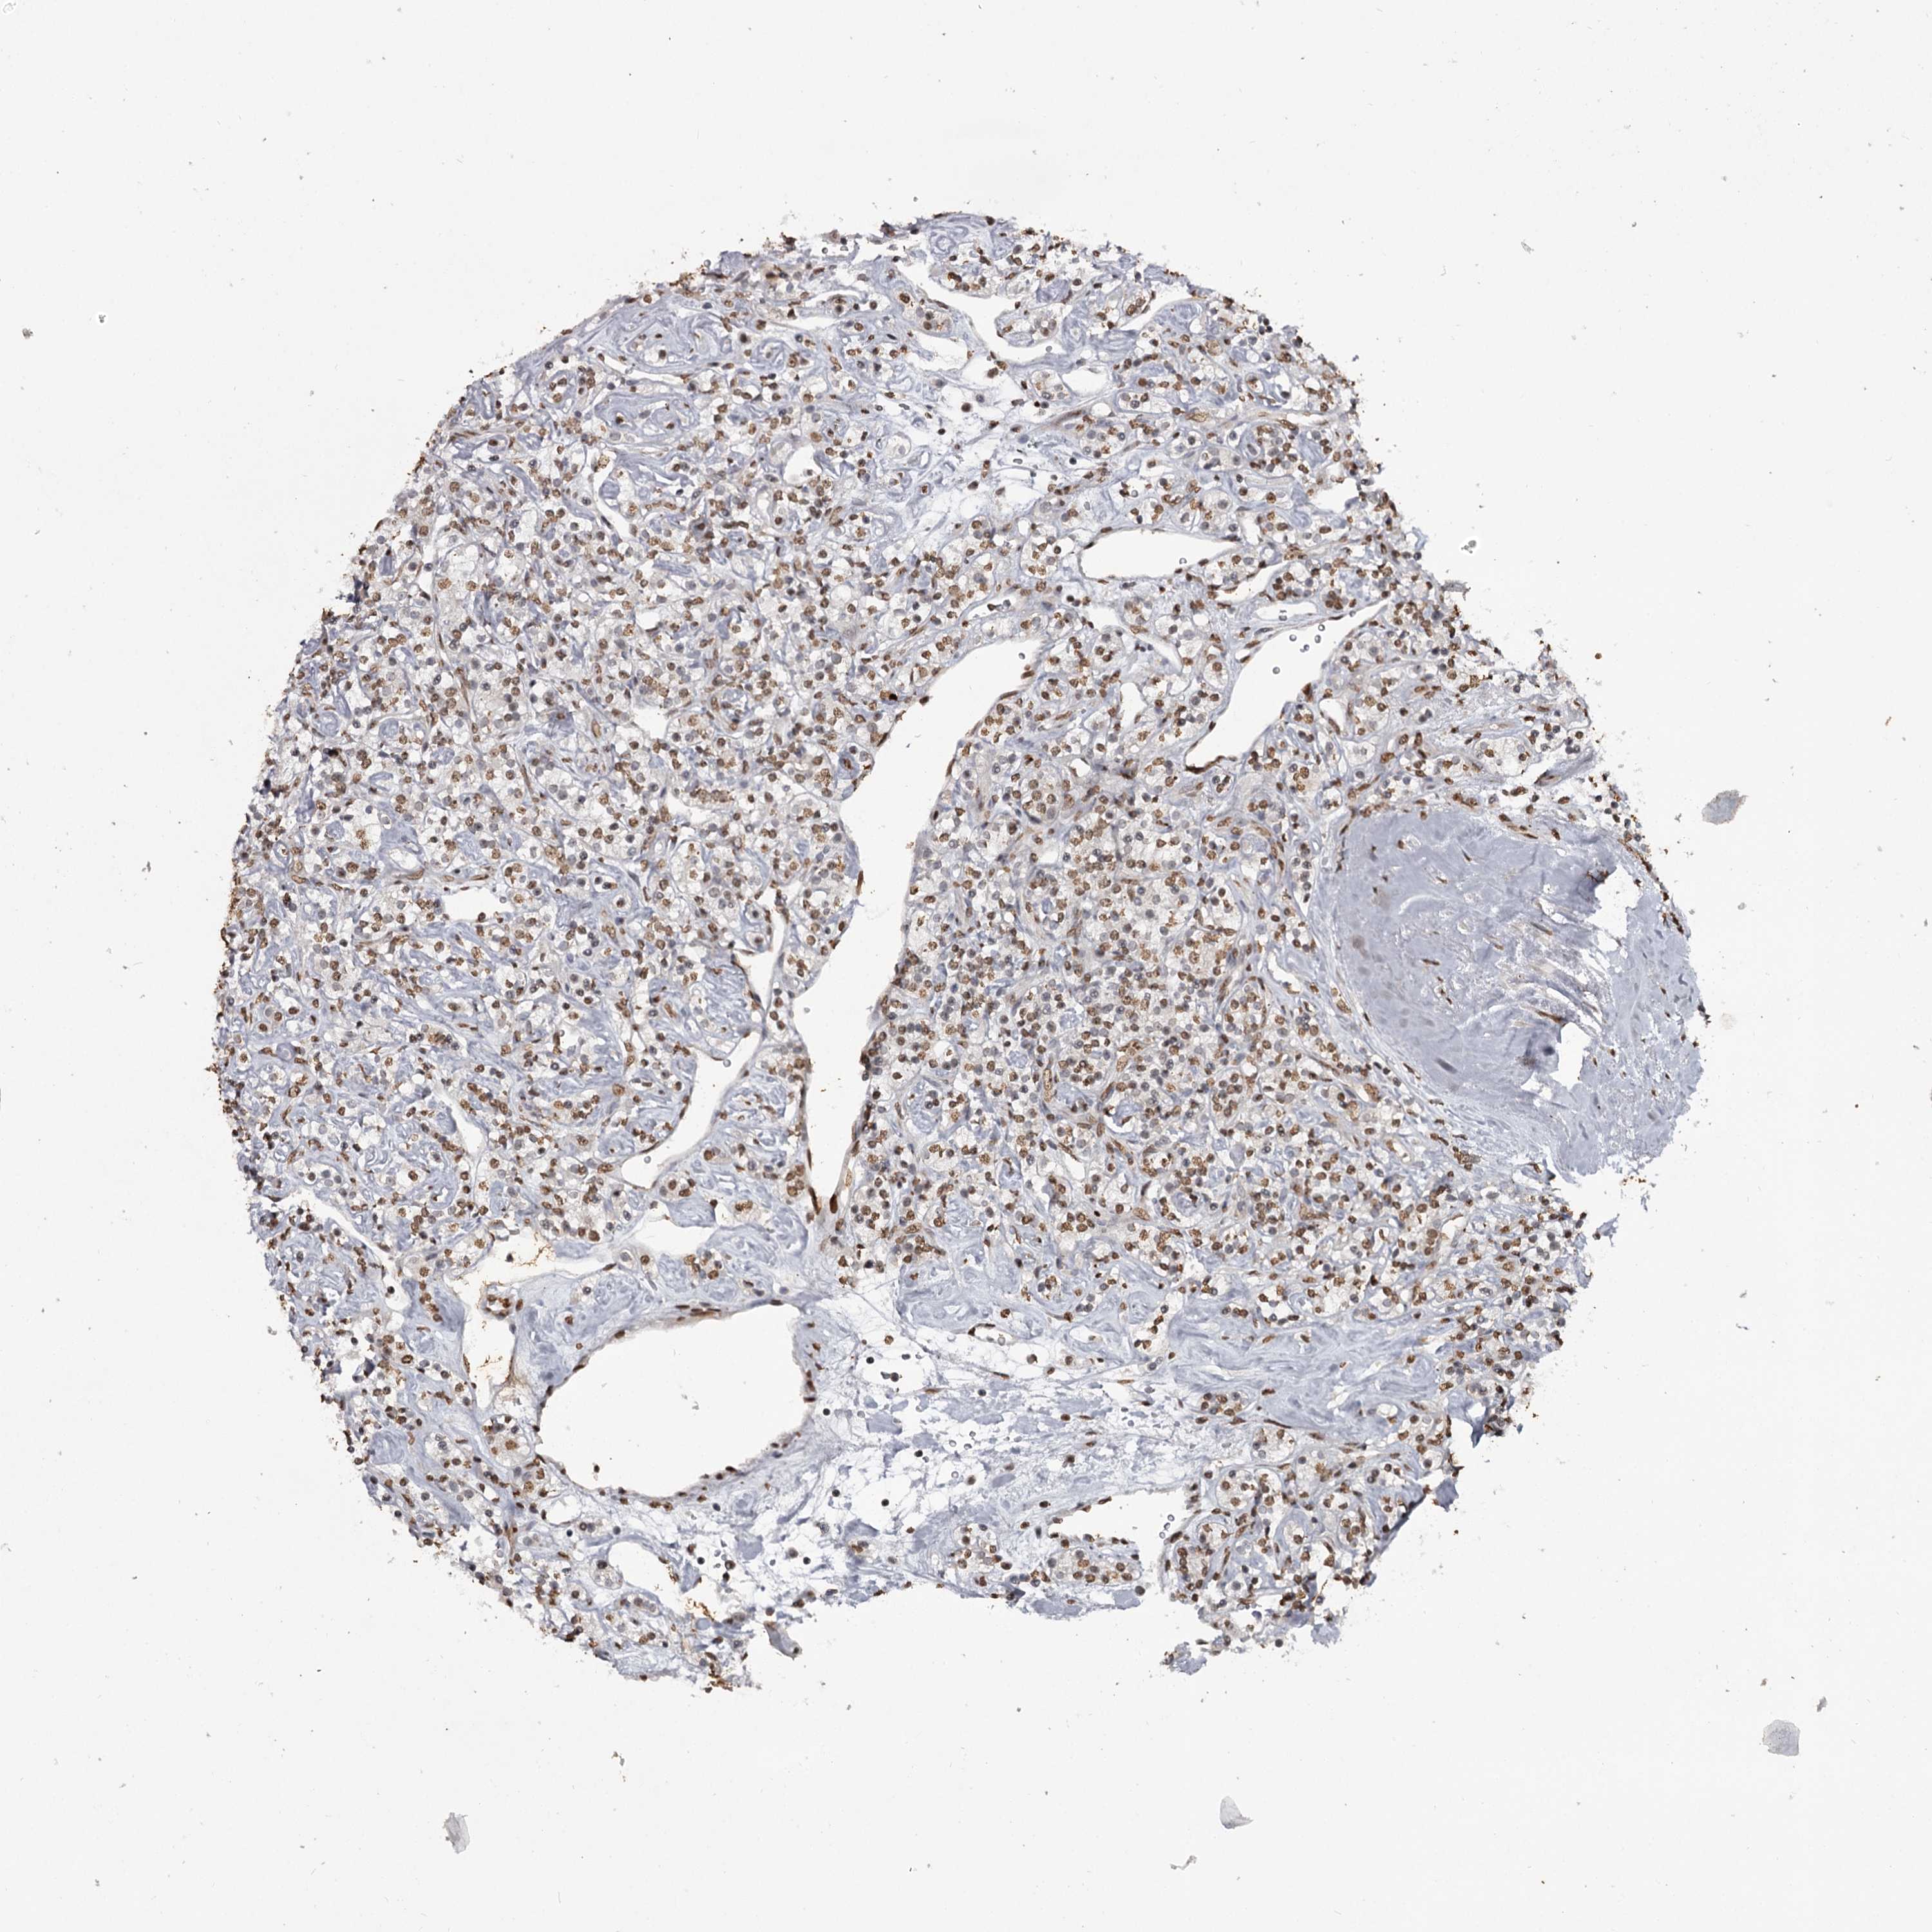

KIDNEY RENAL CLEAR CELL CARCINOMA (VALIDATION) - Interactive survival scatter ploti

The Survival Scatter plot shows the clinical status (i.e. dead or alive) for all individuals in the patient cohort, based on the same data that underlies the corresponding Kaplan-Meier plots. Patients that are alive at last time for follow-up are shown in blue and patients who have died during the study are shown in red.

The x-axis shows the expression levels (FPKM) of the investigated gene in the tumor tissue at the time of diagnosis. The y-axis shows the follow-up time after diagnosis (years). Both axes are complimented with kernel density curves demonstrating the data density over the axes. The top density plot shows the expression levels (FPKM) distribution among dead (red) and alive patients (blue). The right density plot shows the data density of the survived years of dead patients with high and low expression levels respectively, stratified using the cutoff indicated by the vertical dashed line through the Survival Scatter plot. This cutoff is automatically defined based on the FPKM cutoff that minimizes the p-score. The cutoff can be changed by dragging the vertical line or by entering a cutoff value in the square labeled "Current cut-off".

Under the Survival Scatter plot the p-score landscape (black curve; left axis) is shown together with dead median separation (red curve; right axis). Dead median separation is the difference in median mRNA expression between patients who have died with high and low expression, respectively. It is calculated as follows: median FPKM expression of dead patients with high expression - median FPKM expression of dead patients with low expression. This is intended to aid the user in visually exploring custom cutoffs and the associated p-scores and dead median separation.

Individual patient data is displayed and can be filtered by clicking on one or more of the category buttons on the top of the page. Categories describing expression level and patient information include: high, low, alive, dead, female, male and tumor stages. The scale of the x-axis can be toggled between linear and log-scale by clicking on the "x log" button. Mouse-over function shows TCGA ID, patient information and mRNA expression (FPKM) for each patient.

& Survival analysisi

Kaplan-Meier plots summarize results from analysis of correlation between mRNA expression level and patient survival. Patients were divided based on level of expression into one of the two groups "low" (under cut off) or "high" (over cut off). X-axis shows time for survival (years) and y-axis shows the probability of survival, where 1.0 corresponds to 100 percent.

THYN1 is not prognostic in Kidney Renal Clear Cell Carcinoma (validation)

Best expression cut offi

Based on the FPKM value of each gene, patients were classified into two groups and association between prognosis (survival) and gene expression (FPKM) was examined. The best expression cut-off refers the FPKM value that yields maximal difference with regard to survival between the two groups at the lowest log-rank P-value. Best expression cut-off was selected based on survival analysis .

When clicking on this number, the vertical dashed line indicating cut-off, the interactive survival plot, and the Kaplan-Meier curve will be adjusted to show results based on the best expression cut-off.

: 39.03

P scorei

Log-rank P value for Kaplan-Meier plot showing results from analysis of correlation between mRNA expression level and patient survival.

N/A

TCGA RNA samplesi

RNA-seq data is reported as average FPKM (number Fragments Per Kilobase of exon per Million reads), generated by the The Cancer Genome Atlas (TCGA) .

Normal distribution across the dataset is visualized with box plots, shown as median and 25th and 75th percentiles. Points are displayed as outliers if they are above or below 1.5 times the interquartile range. FPKM values of the individual samples are presented next to the box plot.

Average pTPM 38.5

Number of samples 100